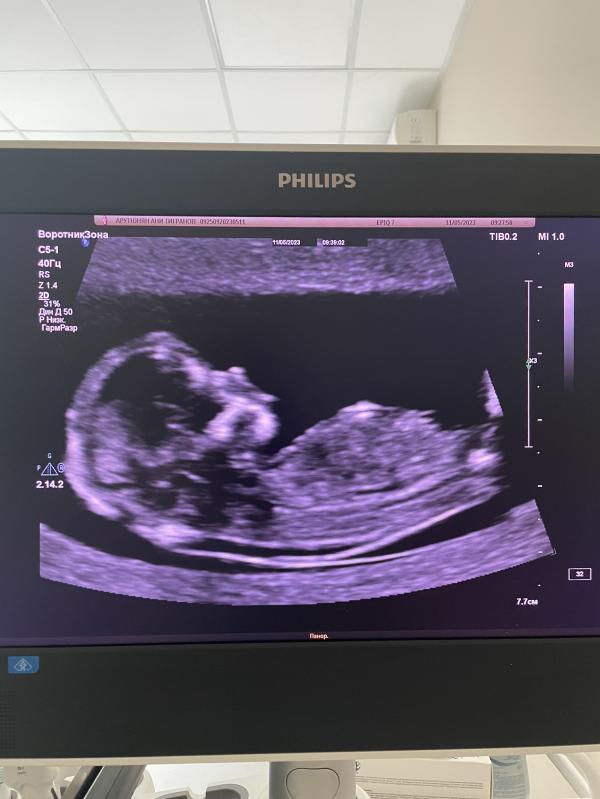

Сегодня была на первом скрининге☺️ малыш растет здоровым и опережает срок на неделю…КТР у нас 70мм.

Так же врач сказал что знает пол малыша на 95% но она написала в конверте(для Гендер Пати) она на этом же сроке она сказала пол второго ребенка!